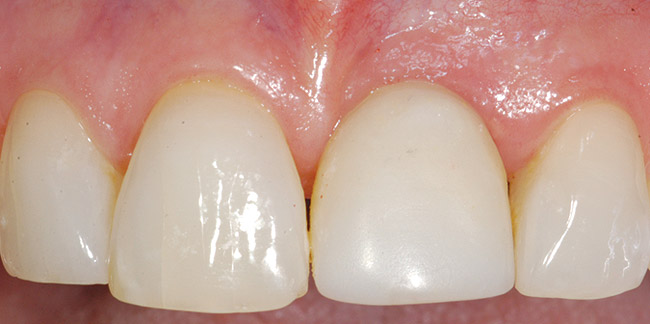

Figure 15  Completed crown. Note short distal papilla secondary to lack of appropriately placed point contact.

Figure 15